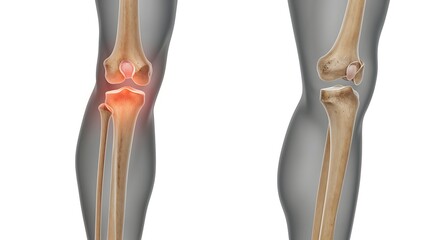

Podobny obraz Medical Elbow Anterior View X-Ray Radiograph Illustrating...